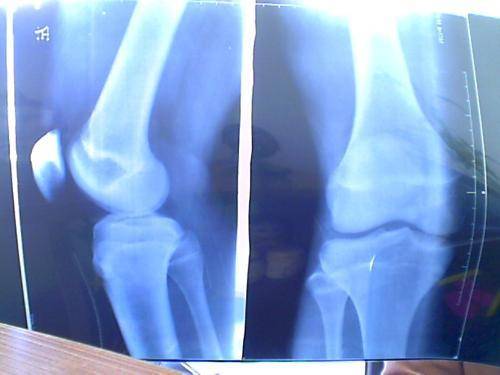

我的朋友最近向我抱怨说 , 特别发愁孩子的身高 , 他家孩子名字叫童童 , 本年10岁上小学 , 平常学习成绩特别好 , 一向名列前茅 , 可是身高却很矮 , 从一年级到现在一向坐在第1排 , 就在前几天的体检傍边查出了骨骼线提早闭合、骨龄超前、发育中止的症状 , 这着实是使家里人惊了一下 , 一向认为宝宝不长个是因为发育晚 , 没想到竟然是身体呈现了毛病 , 毕竟孩他爸将近1米8的大个子 , 孩子却没能遗传他爸爸的身高 。